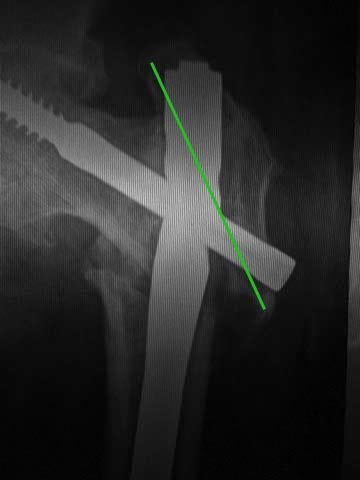

Про динамизацию забыли написать. Но проблема из без нее очевидна. Типичная ошибка с "диагональным" положением гвоздя. Т.е. латеральная точка введения и направление к медиальной стенке центрального отломка. Как он должен бы располагаться - зеленая линия на картинке. Соответственно, надо пересинтезировать аналогичным имплантатом, не повторив этой ошибки. Наверно, можно в шейку в передне-заднем направлении ввести 1-2 винта в проекции канала от lag screw.

если приложить малость фантазии и мысленно выполнить репозицию , то направление винта совпадет с зеленой линией. Деформация гвоздя, смещение, вот и картина псевдо- неправильно заданного направления

если приложить малость фантазии и мысленно выполнить репозицию , то направление винта совпадет с зеленой линией

C зеленой линией должно было совпадать направление не винта, а гвоздя. И исли бы гвоздь был введен по этой линии, то у этого пациента было бы все хорошо, и мы бы не узнали о его существовании.